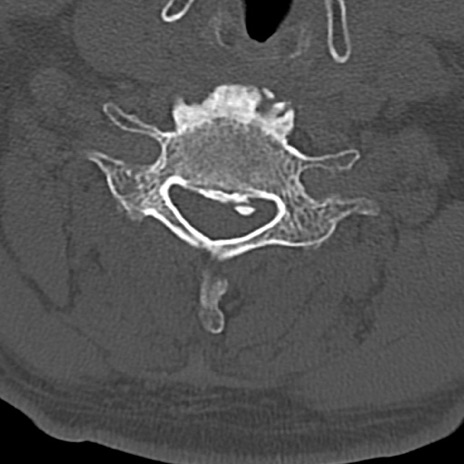

頚椎CT

横断像